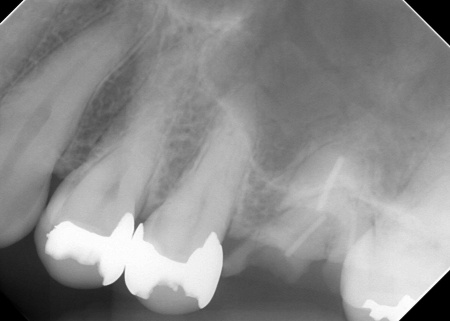

レントゲン撮影をして詳しく検査したところ、複数の小さな虫歯が見られました。

また右上奥歯には、歯根の先に炎症が起きて膿が溜まる根尖性(こんせんせい)歯周炎が認められます。

②根尖性歯周炎を発症している右上奥歯には、歯根内の細菌を除去して薬を詰める「根管治療」を実施し、歯の温存を図ります。患者様は、以前同じ歯に根管治療を行った経験があったため「再根管治療」となります。

次に、右上奥歯の古い材料(以前の根管治療に使用したもの)を除去し、歯根内部の洗浄と消毒をしてから新しい材料で密封し、被せ物を作製して装着しました。